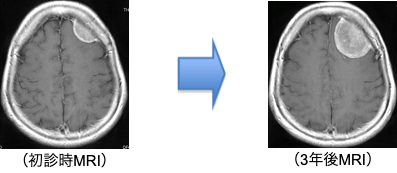

この症例は、当初軽度の頭痛を主訴にMRIを行なったところ左前頭葉に2cmほどの腫瘍が偶然発見されました(左)。ほとんど症状が無く、日常生活に支障がなかったため、1年に1度検査を行い、経過観察していましたが、3年後に4cmとなりました(右)。それでも頭痛は軽かったのですが、腫瘍のサイズが少しずつ大きくなってきたため本人も不安となり、相談の上、開頭手術を行なった症例です。

このように脳の表面にできた場合は、いきなり手術を決断しなくても、治療を受けるか否か検討する猶予はありますので、よく考えたほうが良いです。